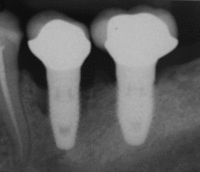

An implant is tested between 8 and 24 weeks to determine if it is integrated. There is significant variation in the criteria used to determine implant success, the most commonly cited criteria at the implant level are the absence of pain, mobility, infection, gingival bleeding, radiographic lucency or peri-implant bone loss greater than 1.5 mm.[37]

Dental implant success is related to operator skill, quality and quantity of the bone available at the site, and the patient's oral hygiene, but the most important factor is primary implant stability.[38] While there is significant variation in the rate that implants fail to integrate (due to individual risk factors), the approximate values are 1 to 6 percent[14](p68)[21]